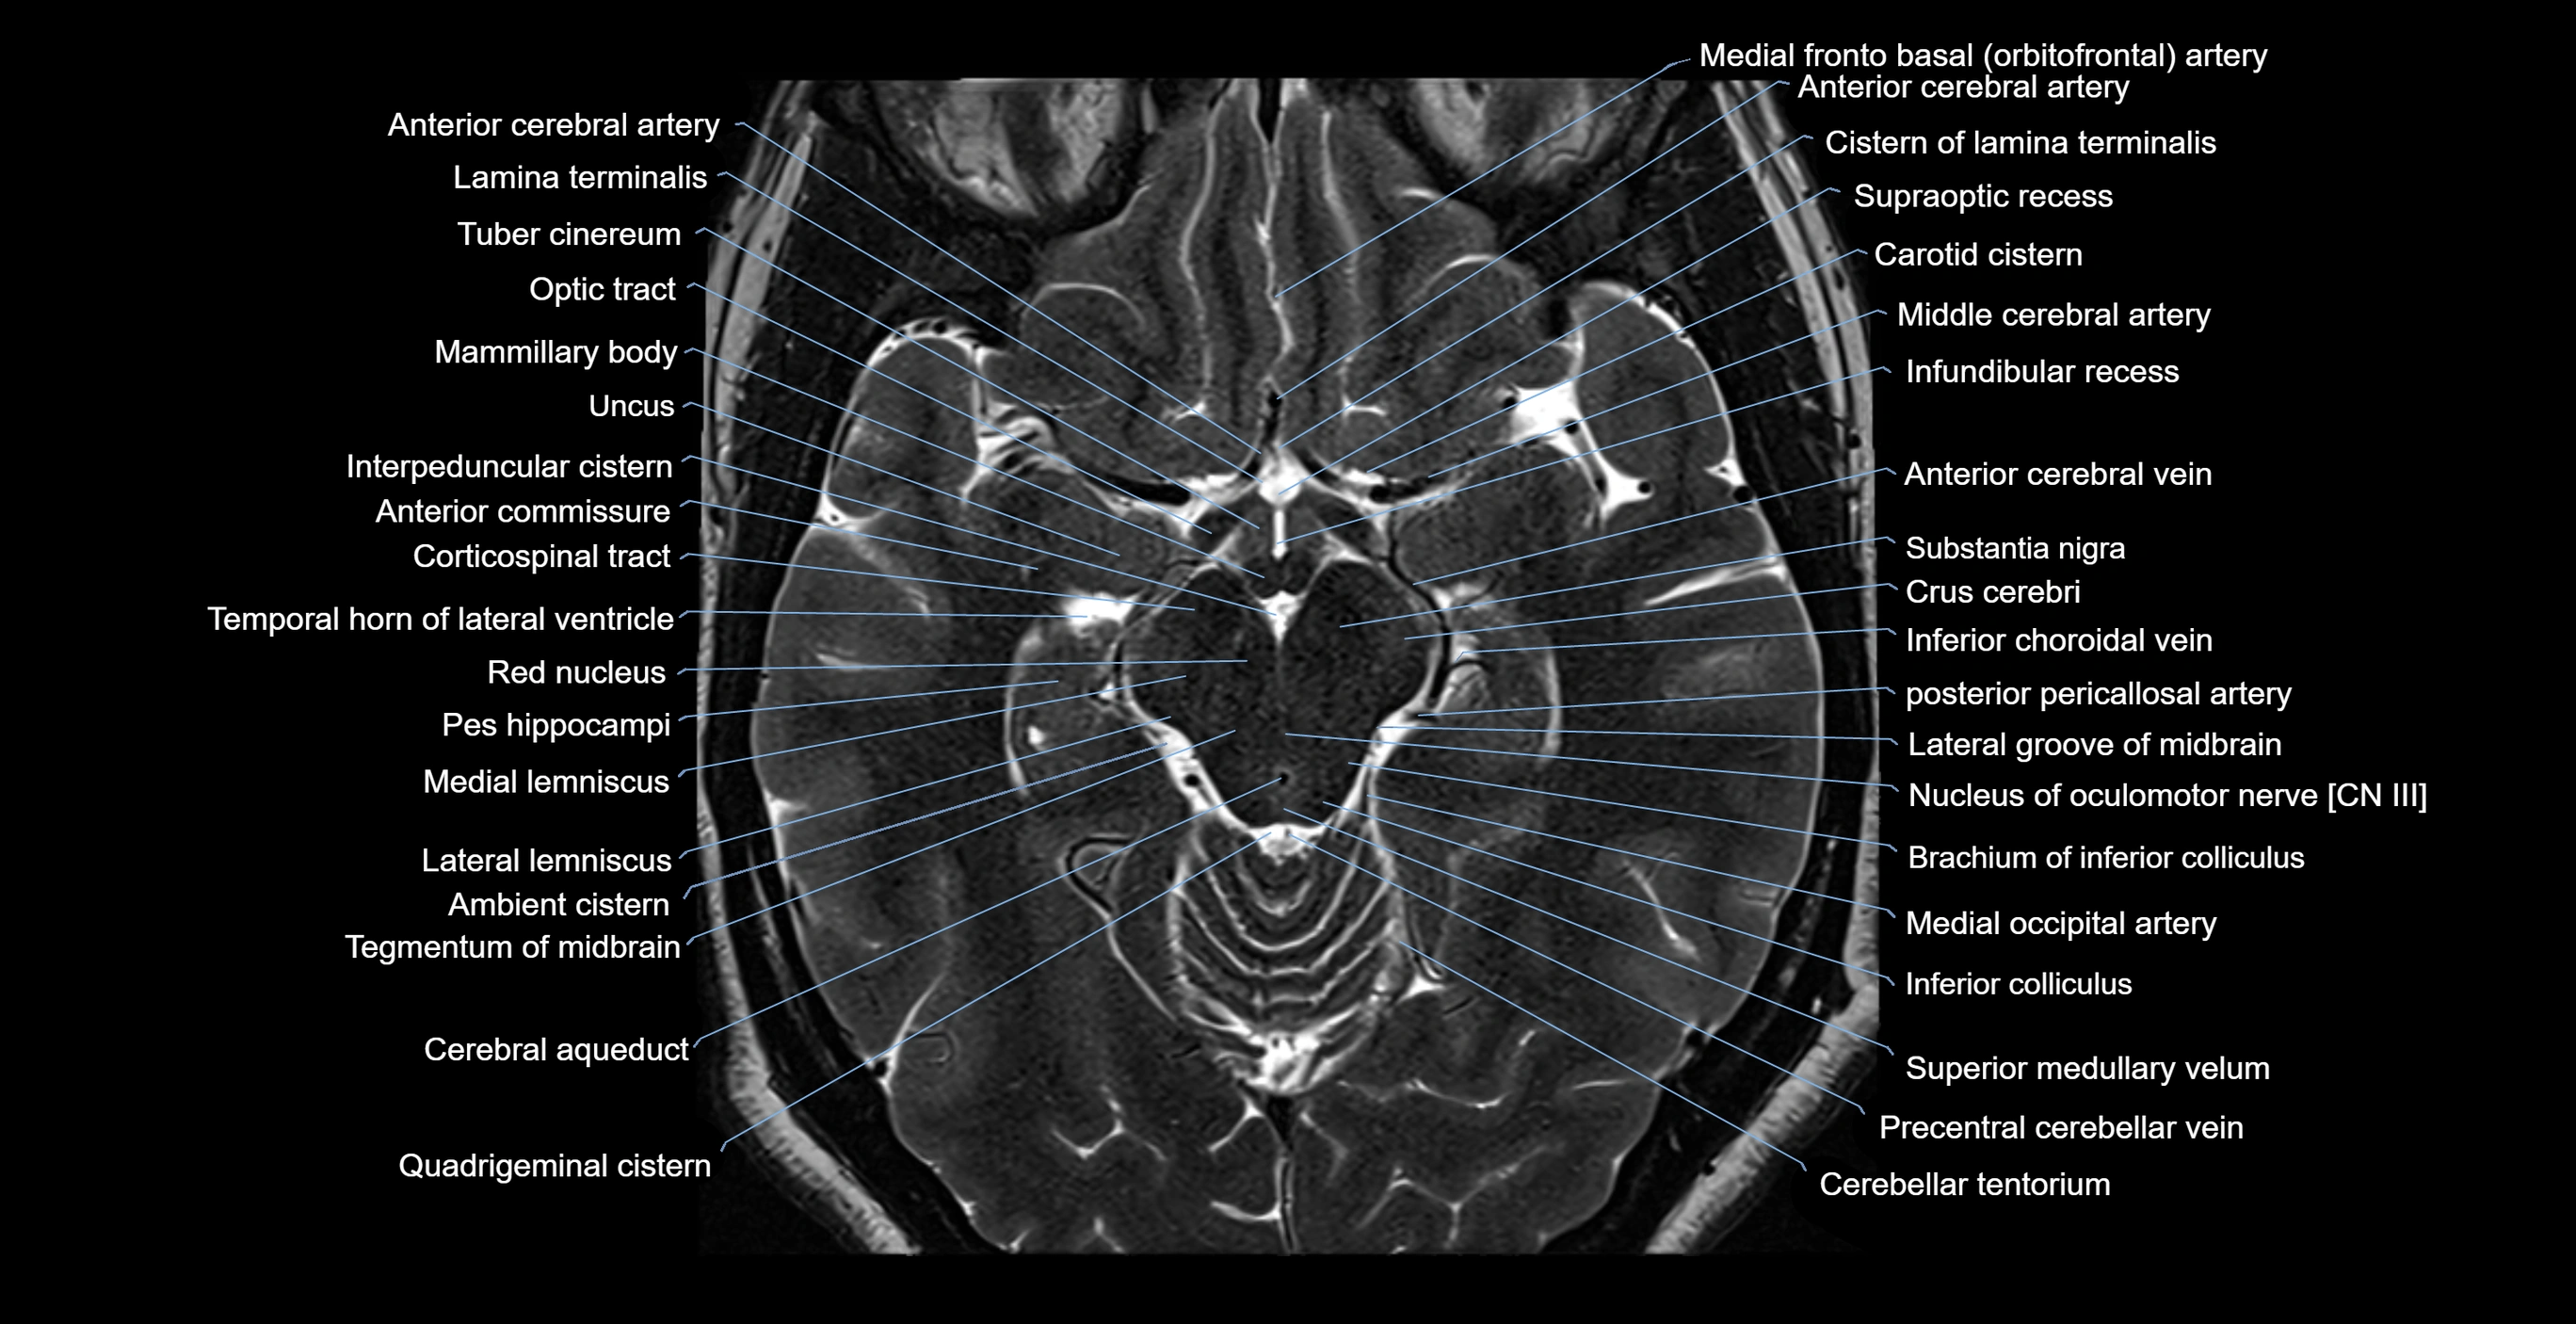

MRI images